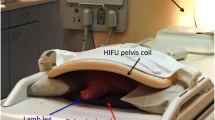

In vivo temperature monitoring

Focused ultrasound ablation was also performed in a swine model. All experimental procedures were done in accordance with National Institutes of Health (NIH) guidelines for humane handling of animals and received prior approval from the University of California San Francisco Institutional Animal Care and Use Committee (approval number: AN088193). The animal was positioned in the left decubitus position onto a gel pad over the ExAblate in-table transducer (Fig. 1) using a frequency of 1 MHz. A total of 12 sonications were performed on the distal diaphysis (six sonications, 35 W, 20 s) and proximal diaphysis (six sonications, 17 W, 40 s) of the femur. As in the ex vivo validation, the focus was placed inside the medullary cavity. At the end of the focused ultrasound procedure, pre- and post-contrast 3D fast spoiled gradient echo (SPGR) images were acquired.